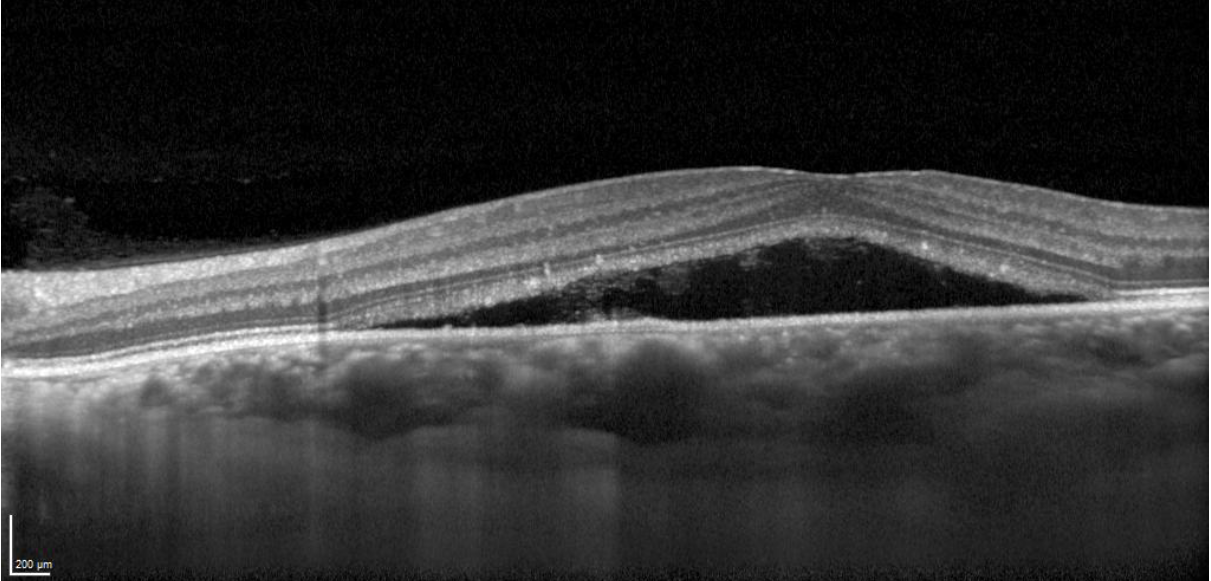

La OCT muestra un desprendimiento neurosensorial de la retina. Destacamos una elongación de los fotorreceptores, hacia el lado nasal de la fóvea se aprecia contenido hiperreflectivo en el espacio subretiniano, cierta excavación sobre el techo de la elongación de los fotorreceptores. Y coincidiendo con el punto de fuga, detectamos la presencia de un vaso coroideo de gran dimensión comprimiendo la coriocapilar.